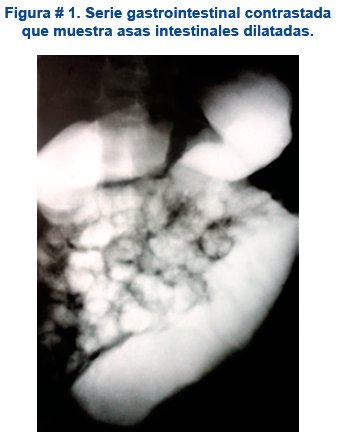

Todos los laboratorios realizados de química sanguínea fueron normales. En los estudios de gabinete, destaca una radiografía simple de abdomen que mostraba una dilatación de la cámara gástrica. La ecografía abdominal, reporto asas intestinales dilatadas con peristalsis intestinal incrementado sobre todo en el hemiabdomen superior, datos que fueron compatibles con una suboclusión intestinal. En la serie gastrointestinal contrastada, se observó una dilatación de la cámara gástrica con buen pasaje del contraste hacia duodeno, el que estaba dilatado hasta el ángulo de Treitz; la primera porción del yeyuno presentaba un calibre aumentado donde el contraste pasa en forma sinuosa hasta detenerse de manera transitoria en fosa iliaca derecha, continuando luego, hacia un intestino de aspecto conservado, ver figura # 1.